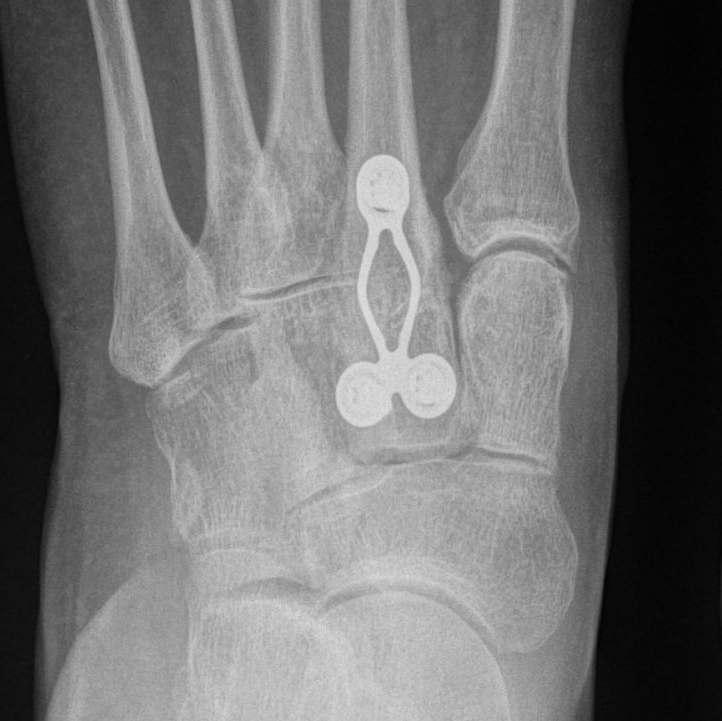

Fusion is permanently stiffening

the bones of a joint together with plates, screws and/or staples. This procedure is also known as arthrodesis.